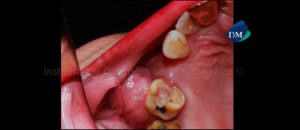

Paciente femenino de 55 años de edad que es referida por presentar dolor en la pieza 26. La radiografía panorámica nos muestra un trazo de